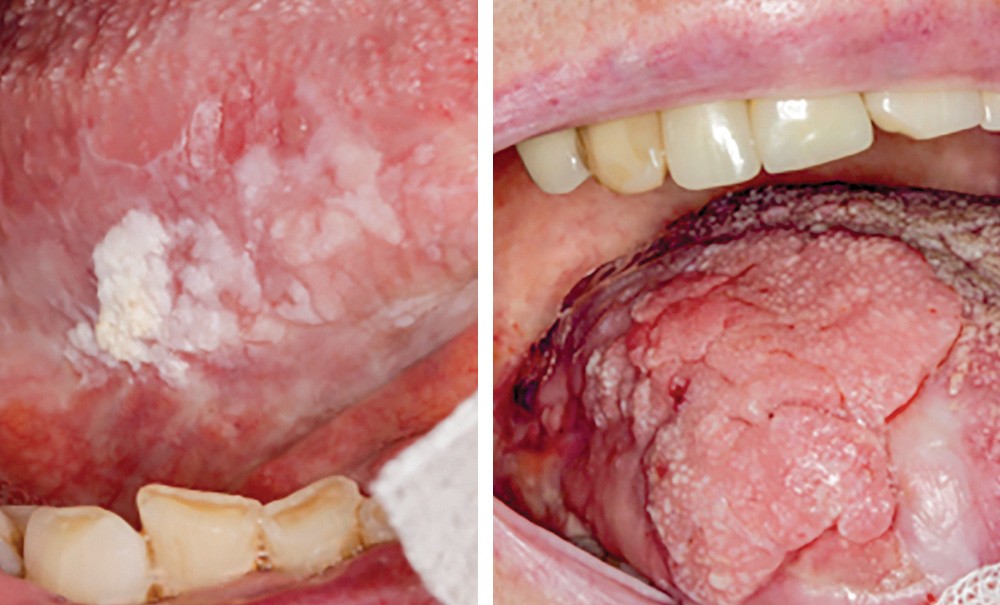

• On observait une volumineuse tumeur verruqueuse, exophytique, de 3 x 4 cm, non douloureuse, siégeant sur le milieu du bord droit de la langue. La surface comportait par endroits de fines digitations et était parcourue par quelques fissures. La protraction linguale n’était pas limitée. À la palpation, il n’y avait pas d’adénopathies cervico-faciales.

• Après un arrêt momentané du Xarelto®, une biopsie a été réalisée à cheval sur la limite antérieure de la tumeur. L’extrémité du prélèvement intéressant la tumeur était ulcérée et montrait une prolifération épithéliale exo- et endophytique, avec des projections papillaires à sommet arrondi, recouvertes d’une couche de parakératose qui, par endroits, s’invaginait entre les massifs épithéliaux. Ces derniers étaient constitués par un épithélium hyperplasique et acanthosique, focalement spongiotique, avec de nombreuses cellules à cytoplasme clair. Dans les couches profondes de l’épithélium, on observait…